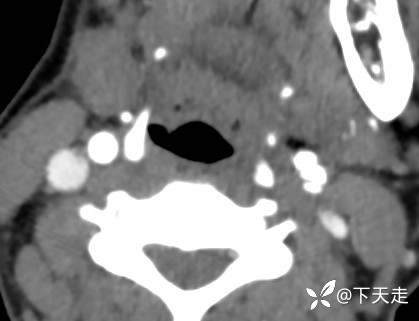

青鹊词 推荐青年女性,37岁,因不能言语就诊于耳鼻喉科,耳鼻喉科医生诊疗后建议神经内科就诊。

相关检验检查资料如下